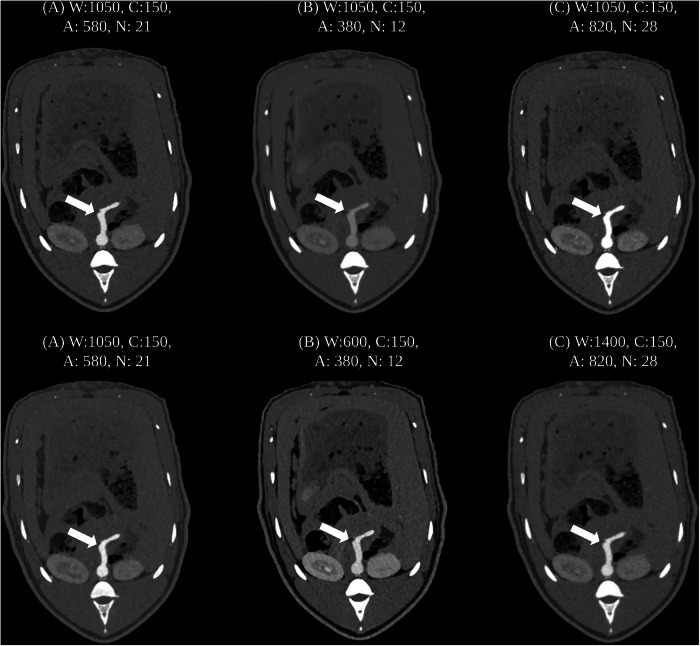

Methods: Six minipigs (median weight: 32.5 kg; IQR: 29.8-34.6 kg) underwent thoracoabdominal CTA using a clinical dual-source PCD-CT at 70 kVp with three scan protocols: (A) reference (100% CM and radiation dose), (B) increased radiation (233%) and reduced CM (56%) dose, and (C) reduced radiation (50%) and increased CM (141%) dose. CNR, subjective image quality, and radiation doses were assessed, with statistical analysis including Mann-Whitney U-test and Kruskal-Wallis tests.

Results: CTDIvol was 1.7 mGy (IQR: 1.5-1.8) for scan A, 4.3 mGy (IQR: 3.8-4.7) for scan B, and 0.9 mGy (IQR: 0.8-1.0) for scan C (p < 0.001). CM volumes were 16 mL (IQR: 15-17) for scan A, 10 mL (IQR: 8-10) for scan B, and 23 mL (IQR: 21-24) for scan C. No significant differences in CNR were found between scans, with medians of 26 (IQR: 24-28) for scan A, 23 (IQR: 22-26) for scan B, and 26 (IQR: 24-30) for scan C (p = 0.276). Subjective image quality was similar across scans (p = 0.342).